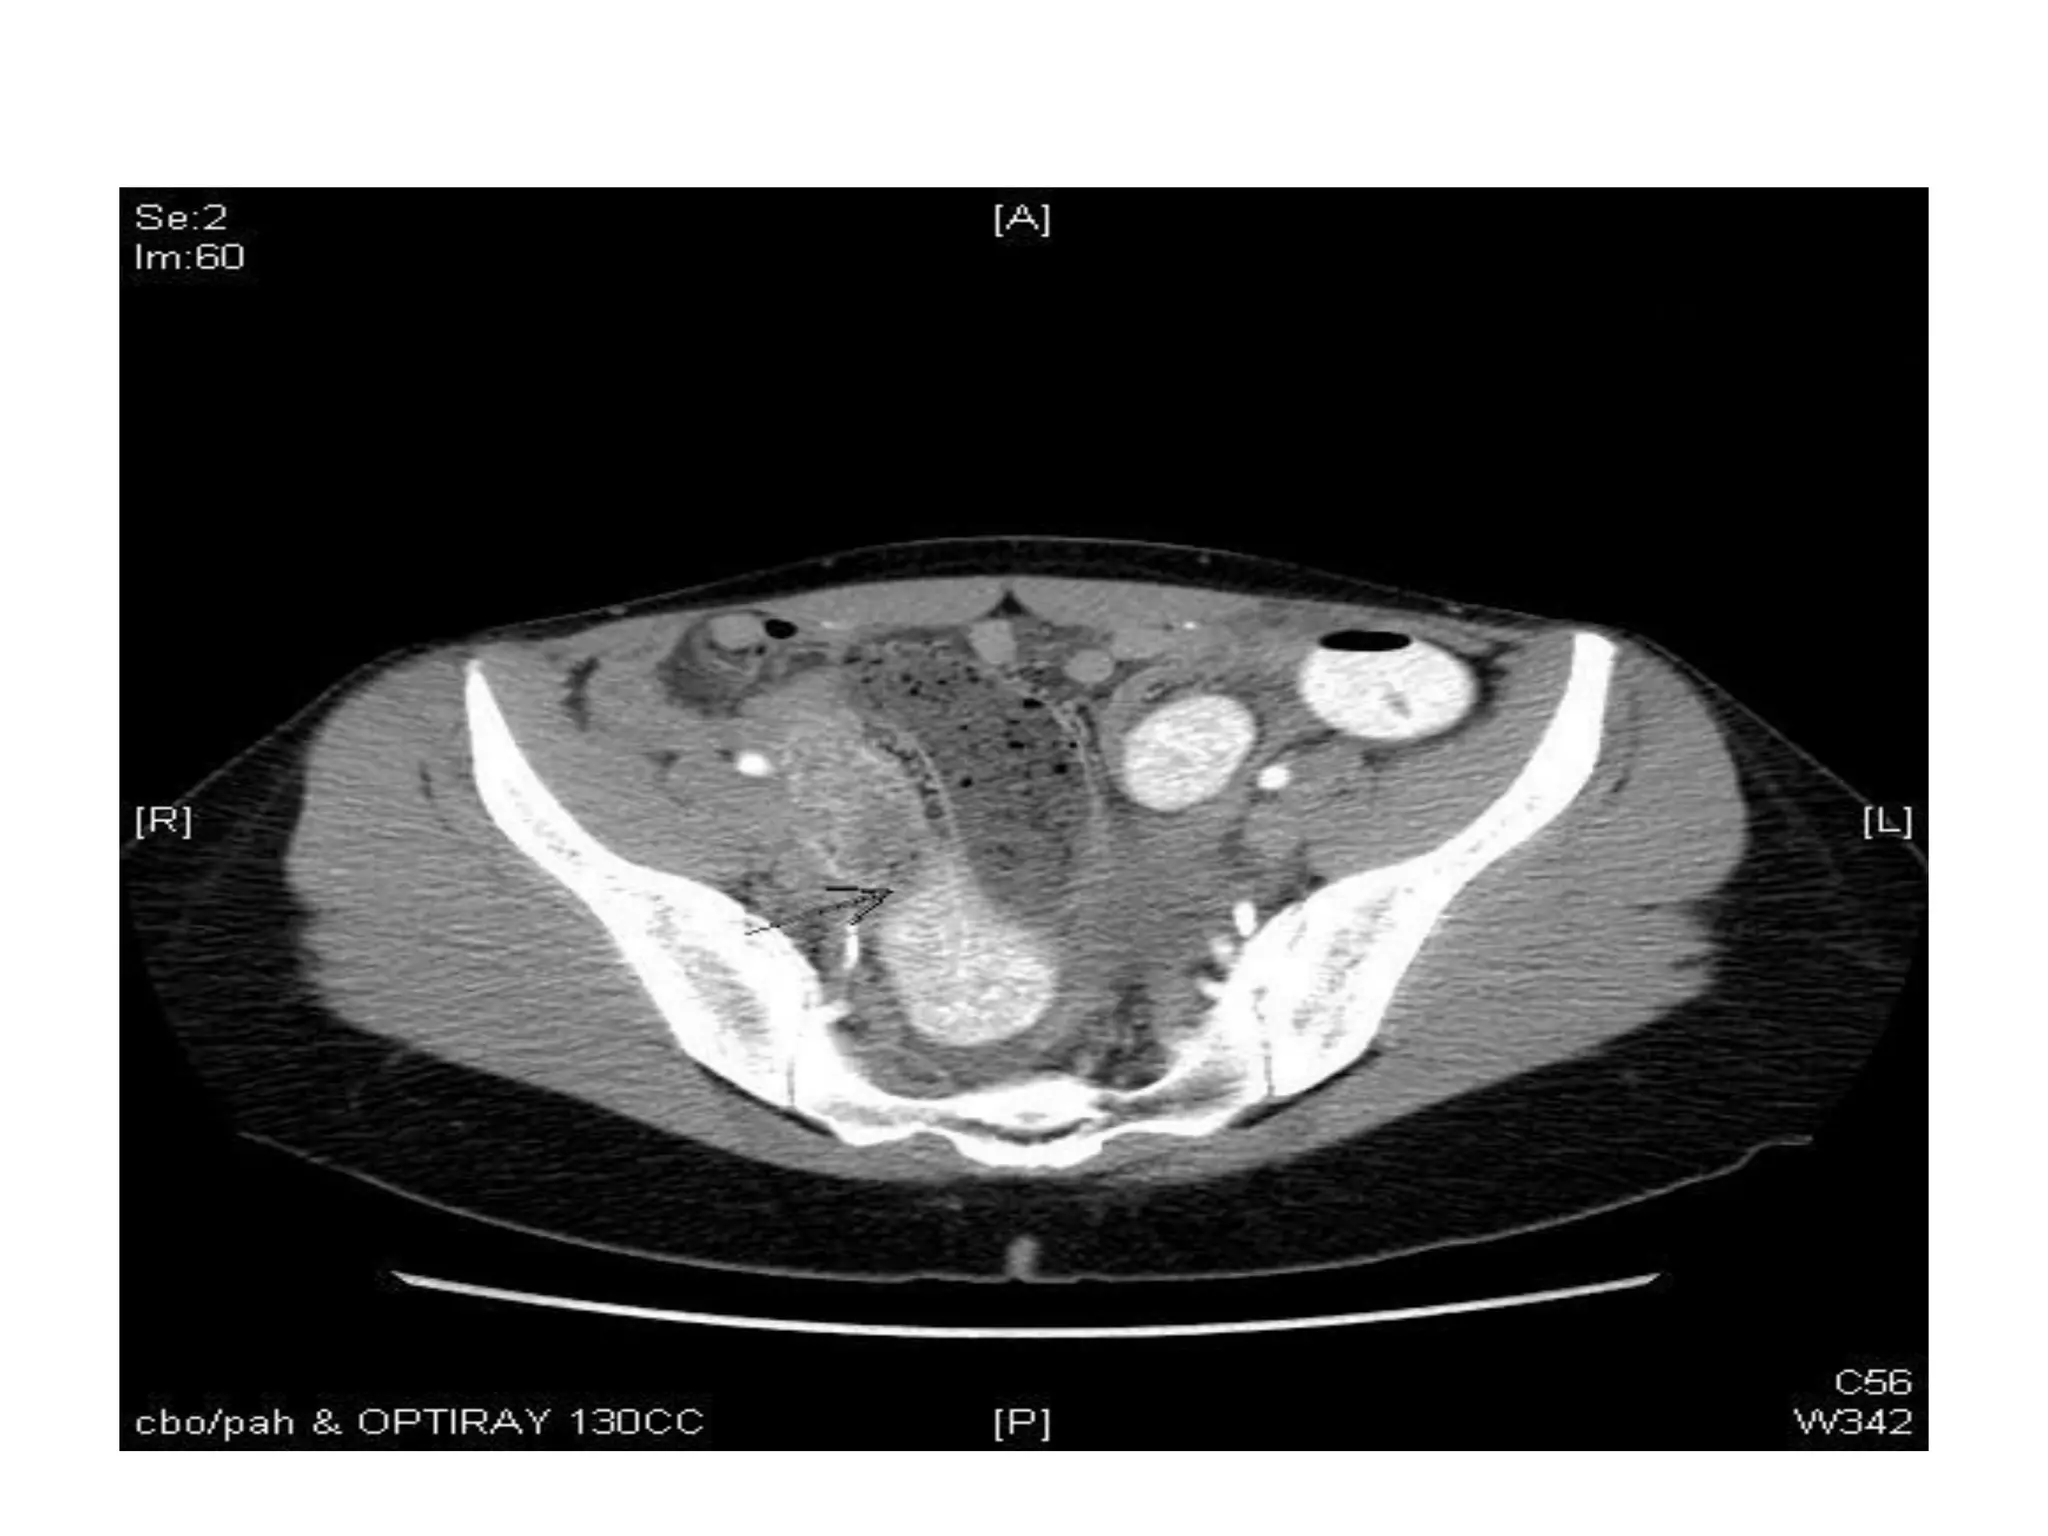

C T

• Not typically used b/c findings are nonspecific

• Endometriomas appear as cystic masses

• Can show high attenuation lesion with

dependent fluid

• Good for complications of endometrioma like

bowel and ureteral obstruction